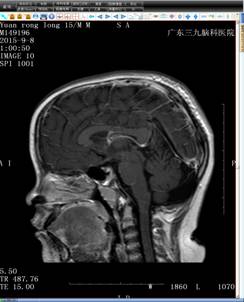

结合小袁的病史,神经内二科的钟水生主任考虑其存在垂体柄阻断综合征的可能(图一),并建议补充垂体薄层平扫+增强扫描(图二)。完善检查后,钟主任给予小袁B族维生素、申捷促进神经修复等对症治疗。

头颅MRIT2+增强(矢状位)+FLAIR(图一)